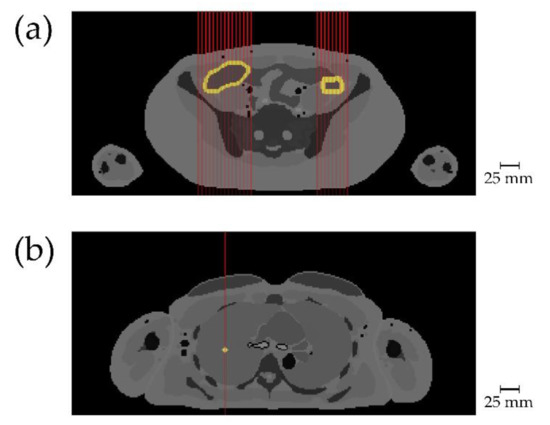

3.2. Abdomen

3.2.2. Dependence on Incident Beam Angle